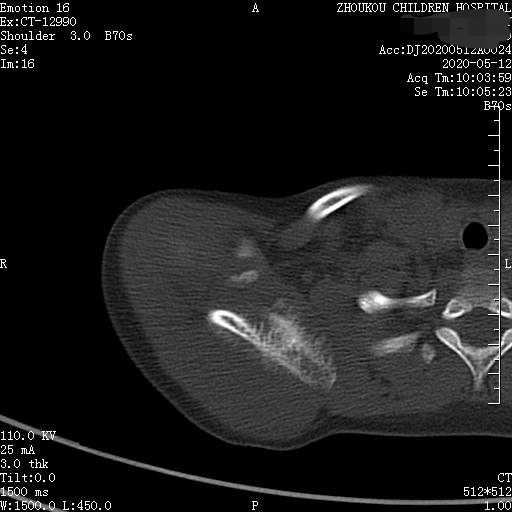

通过CT平扫发现:右侧肩胛骨骨质密度不均,骨质内可见“虫食样”低密度影,骨质边缘可见多发放射状骨针,呈“日光射线征”。周围软组织明显肿胀,肌间隙模糊。CT检查意见:考虑:右肩胛骨占位,骨肉瘤可能,不除外其它恶性肿瘤病变,请结合临床及相关检查注意复查。 影像鉴别诊断:骨肉瘤是指起源于骨间叶组织,遗留形成骨细胞直接形成骨样组织为特征的恶性肿瘤,是比较常见的骨恶性肿瘤,好发于十到二十岁青少年,骨肉瘤常见于管状骨,股骨远端胫骨近端最多见,表现为疼痛局部肿胀运动障碍,实验室检查都有碱性磷酸酶升高。

二、根据骨质破坏和肿瘤骨的多少,骨肉瘤可以分为三型,液化型以肿瘤新生骨为主,溶骨型是以骨质破坏为主,混合型新生骨的形成和骨质破坏并存,x线表现是不规则的骨质破坏伴浸润,可见日光样和放射状骨膜反应,骨膜新生骨在破坏可形成考特曼三角,骨内可见云状、絮状、针状、放射状肿瘤骨伴软组织肿块而形成。